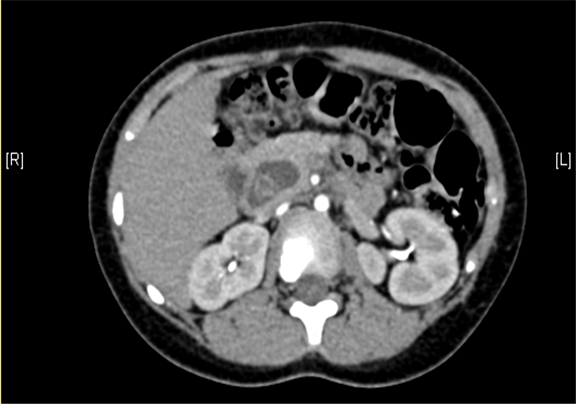

术前CT检查:

动脉期

静脉期

上腹部增强CT:1. 肝内部分胆管-肝门部胆管-胆总管扩张,符合先天性胆管扩张症2. 胆总管下段腔内结节状略高密度影,伪影?结石?3. 胆囊壁略厚,提示胆囊炎可能。